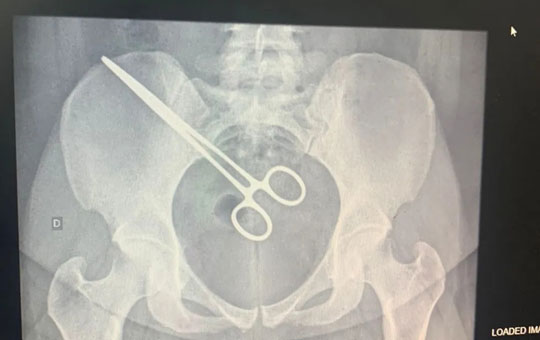

Mulher passa 2 meses com pinça cirúrgica esquecida dentro do corpo

Uma mulher passou por uma cirurgia, na segunda-feira (12), para retirar uma pinça que foi esquecida na região pélvica após um procedimento de retirada de feto na Santa Casa de Araçatuba, no interior de São Paulo. O caso foi descoberto após ela passar mais de dois meses com o objeto no corpo.

Após o episódio no CDP, a paciente foi até a Santa Casa, onde fizeram um exame de raio X e constataram que a pinça estava dentro dela. A mulher foi internada novamente no hospital, na segunda-feira, para cirurgia de retirada do instrumento.